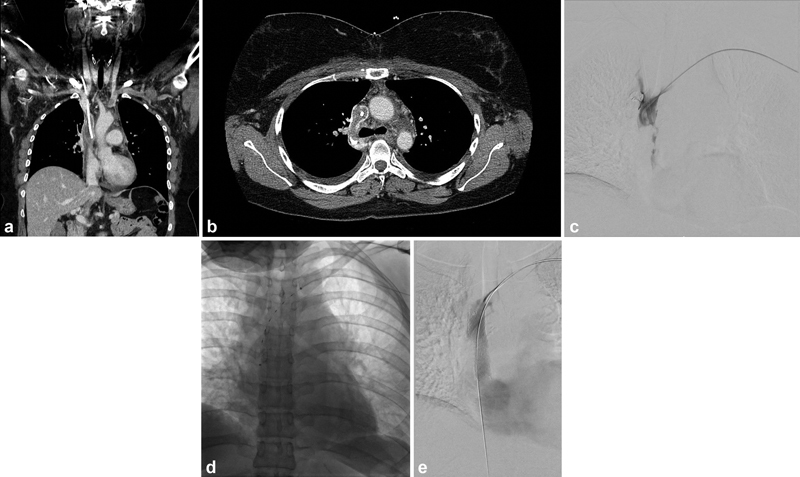

CDT may also be appropriate for patients suffering from severe symptoms after acute secondary UEDVT involving most or all axillary and subclavian veins. 21 However, given that the primary purpose of CDT is to reduce long-term symptoms, the risks of CDT should be carefully weighed against the patients' long-term prognosis relative to their underlying medical conditions. In general, CDT can be considered if patients have severe symptoms that do not respond to anticoagulation, have an active lifestyle that will require vigorous upper extremity movement, and are expected to live long enough for PTS to impact their quality of life significantly. Patients with malignancy should have a CT or MRI of the brain to rule out intracranial neoplasms, which are a contraindication to CDT. Patients with malignant superior vena cava (SVC) syndromes are an exception to the above generalization. Malignant SVC syndrome itself can be life-threatening and often requires urgent CDT and/or endovascular stenting ( Fig. 4 ).

Fig. 4.

A 27-year-old female with a history of Hodgkin's lymphoma presenting with acute upper extremity and facial swelling. A CT scan was performed demonstrating significant thrombus surrounding the port catheter causing superior vena cava (SVC) occlusion ( a —coronal CT, b —axial CT). ( c ) Initial venogram demonstrates extensive thrombus within the SVC. ( d ) The patient underwent aspiration thrombectomy followed by CDT using EKOS. ( e ) The following day the patient underwent SVC stenting with a 16 mm × 60 mm Zilver Vena stent (Cook Medical, Bloomington, IN).